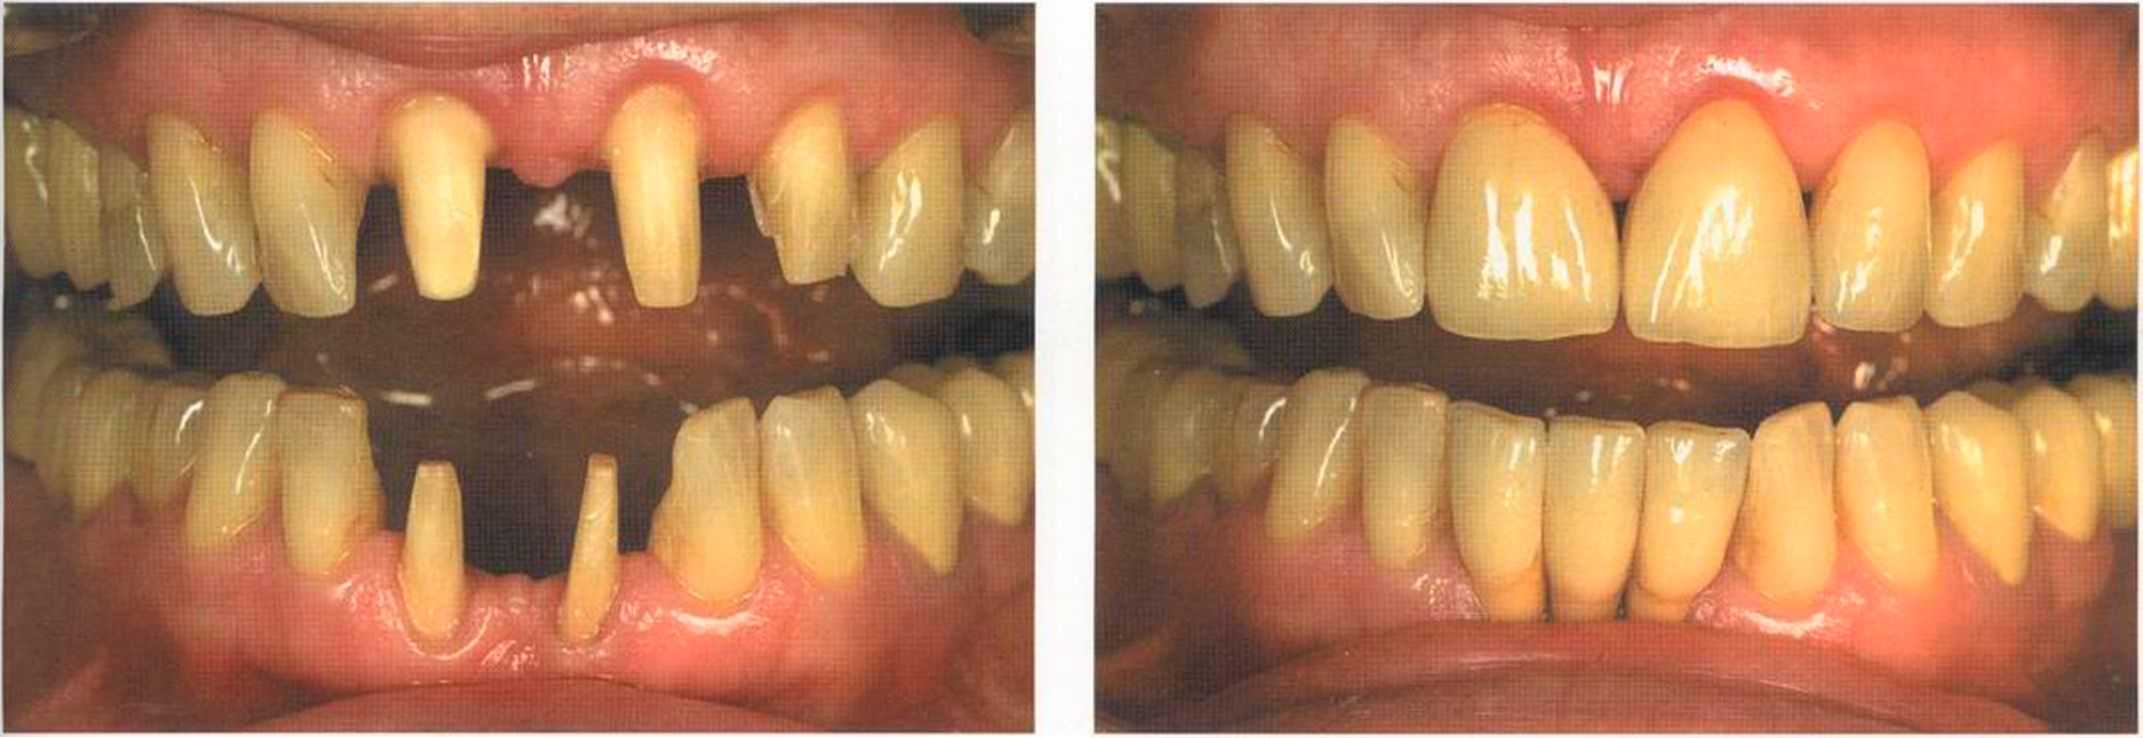

Вспомним, как все начиналось.

Только что зацементированные коронки. До сих пор сохранилось воспаление десневого сосочка. Уже через несколько дней он будет здоровым, бледно-розового цвета.

Окончательный результат и естественный цвет губ. Женщина была очень счастлива и довольна своим новым внешним видом. Наконец мечта осуществилась — нет больше этих щелей на видимом участке. Всей нашей команде было очень приятно видеть радость в ее глазах.